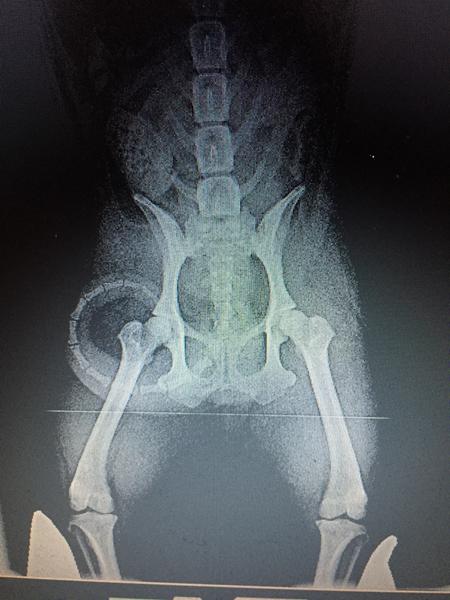

#10   7. jun 2017 Hunden skal ligge på denne måde, og det trænede øje vil kunne se at det her er A hofter.

Bedømt hos DKK